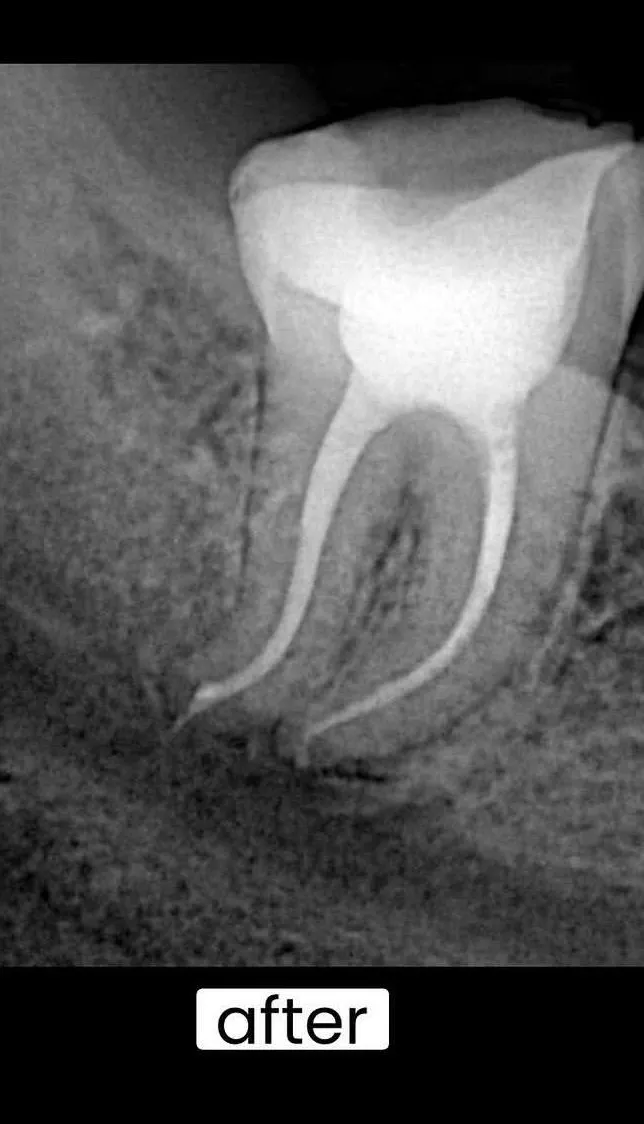

بعد